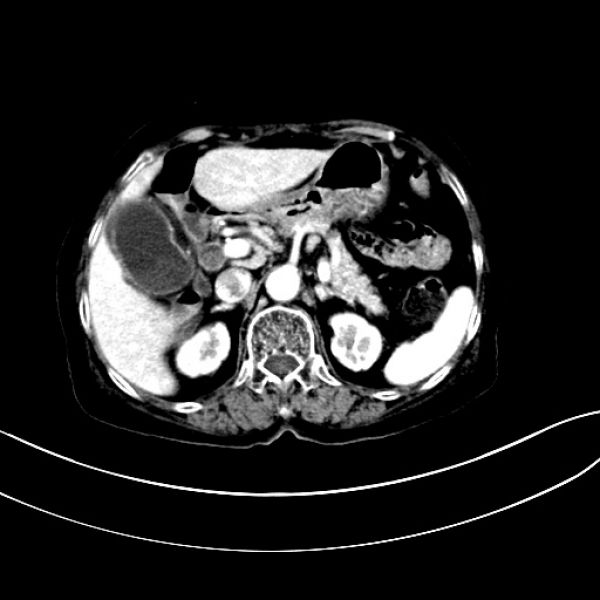

术前增强CT结果